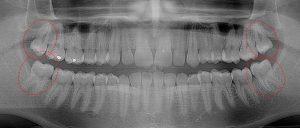

This 34 year old patient has all four third molars present (circled) and fully erupted into occlusion. They appear disease free…but are difficult to keep clean. 3rd molars are the most likely teeth to decay or have gum disease with a >98% probability that decay and gum disease will occur around all four teeth over this patient’s life time.